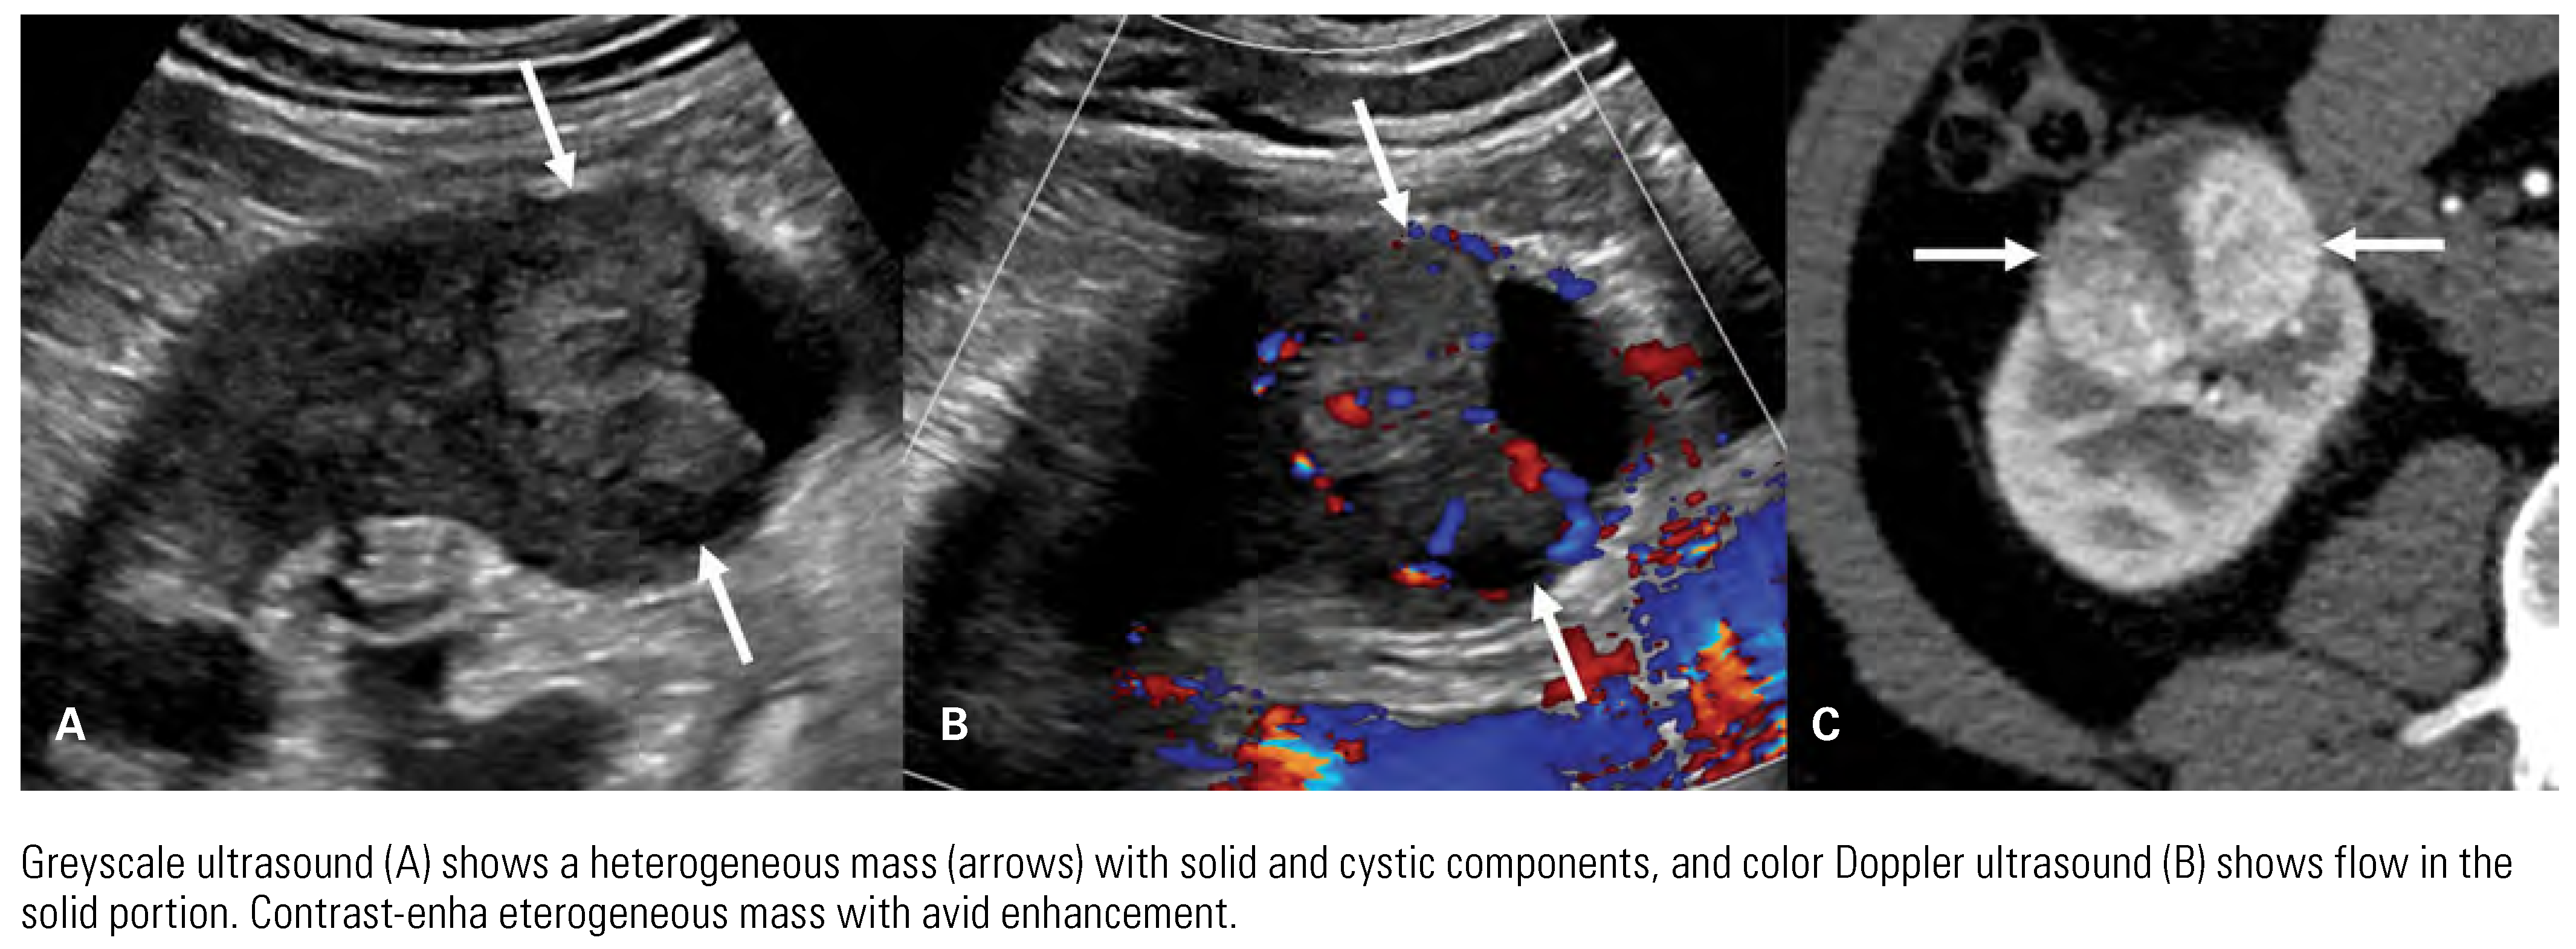

![]() |